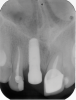

Fig 2. Placement of an implant in a young adult. A female patient had had a congenitally missing maxillary lateral incisor restored when she was 20 years old. Ten years later (Fig 2) the implant-supported restoration was in an infraocclusion state, shorter than the neighboring teeth, due to continuous skeletal growth. Radiograph (Fig 3) showed the marginal bone level of the implant was not affected.

Figure 2

Numerous clinical studies of skeletal changes and alveolar bone growth modifications around single implant-supported restorations in the esthetic zone in growing pigs and human case reports have been published.24-27 This issue has attracted particular attention in young individuals, most of whom required implant therapy due to congenital agenesis or trauma. A topic of thorough discussion among clinicians has been whether to use dental implants in young patients at all to replace missing teeth and, if so, what is the optimal age to place them with regard to possible skeletal changes that might follow. Implants become ankylosed to the bone in an identical way that an avulsed tooth behaves following late re-implantation.28 Such ankylosed teeth as well as dental implants do not adapt to eruptive processes of the surrounding skeletal growth and thus develop infraocclusion, which can severely affect esthetic appearance by the tooth or restoration being shorter than the neighboring teeth, which continue their growth (Figure 2 and Figure 3). Additionally, interproximal contact opening has been observed between the ankylosed crown and nearby natural crowns. Several in vivo experiments that examined osseointegrated implants in young populations concluded that dental implants should not be placed in young patients until their permanent dentition is fully erupted and their skeletal growth completed.29 Such recommendation was even more accentuated when the esthetic zone was involved.